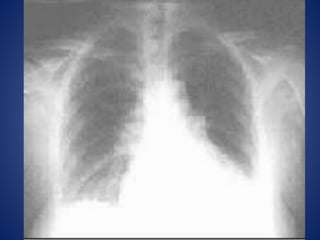

• Radiografía de tórax

Pruebas diagnosticas • Ecografía •Tomografía axial computarizada • Resonancia magnética nuclear • Lavado peritoneal diagnóstico • Laparoscopia • Radiografía de tórax • Placas simples de abdomen

6. Neumonía con reacción pleural